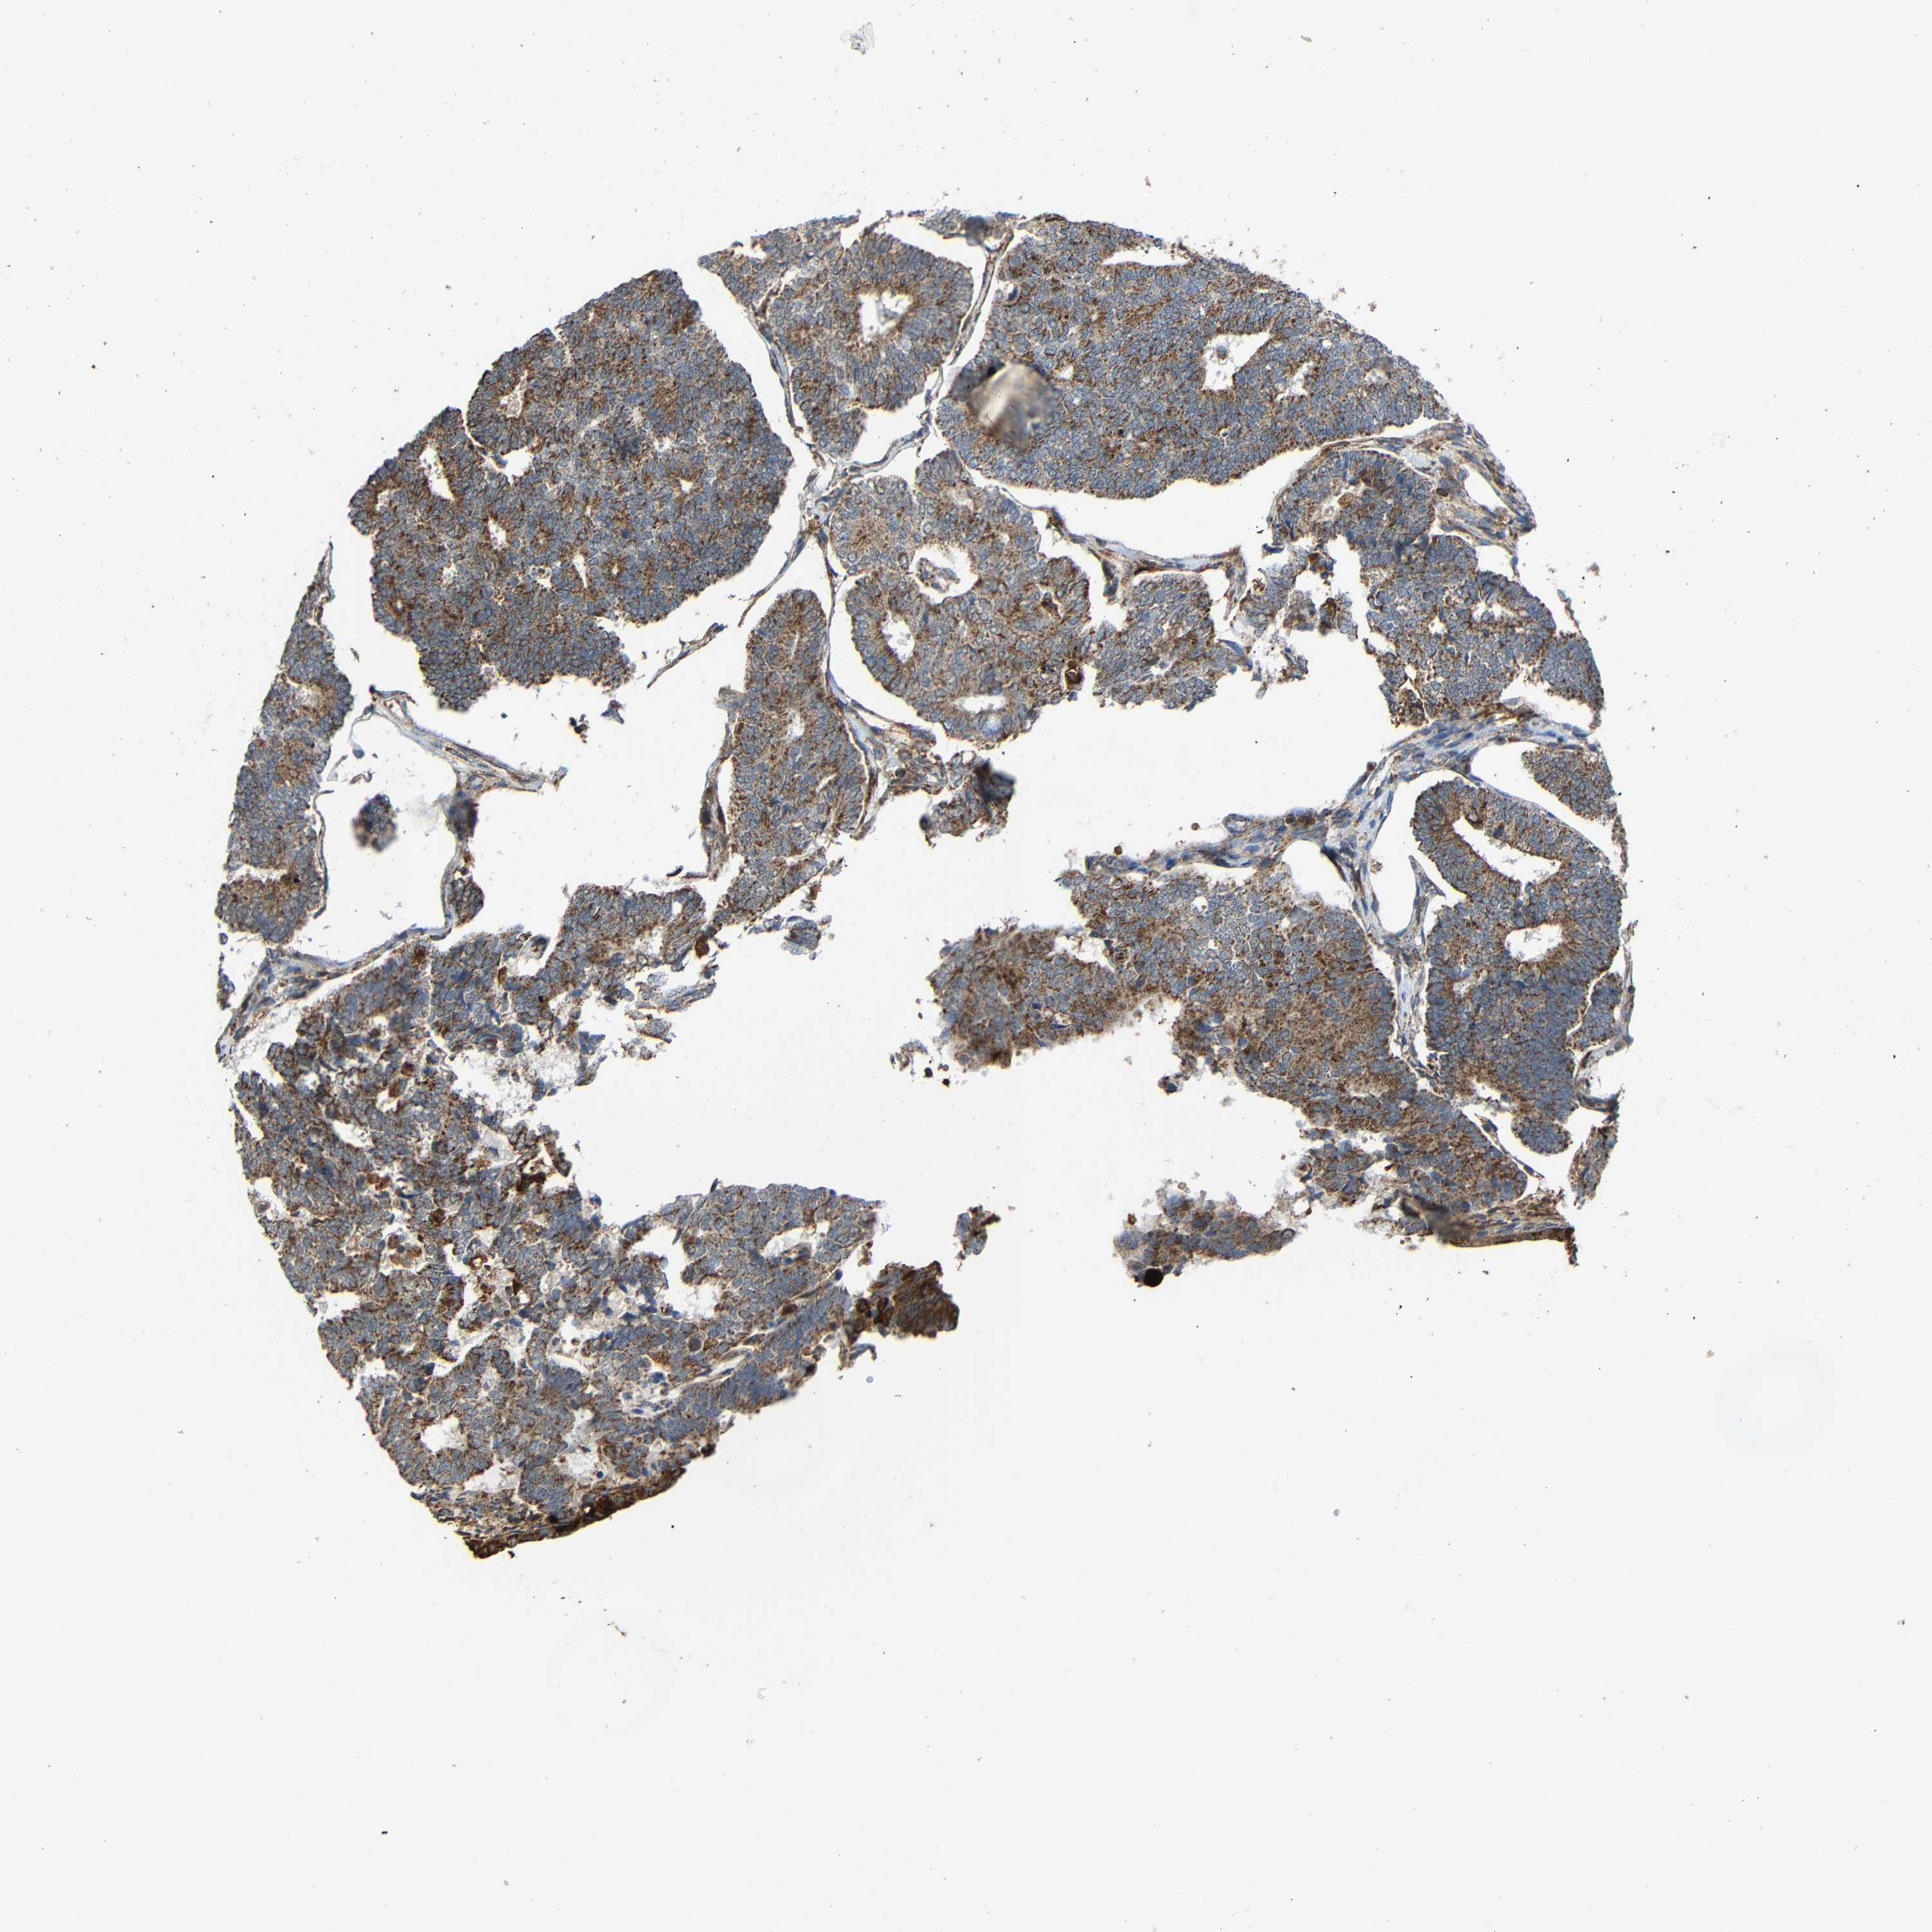

ENDOMETRIAL CANCER - Protein expressioni

A mouse-over function shows sample information and annotation data. Click on an image to view it in a full screen mode. Samples can be filtered based on level of antibody staining by selecting one or several of the following categories: high, medium, low and not detected. The assay and annotation is described here.

Note that samples used for immunohistochemistry by the Human Protein Atlas do not correspond to samples in the TCGA dataset.

Antibody stainingi

Antibody staining in the annotated cell types in the current human tissue is reported as not detected, low, medium, or high, based on conventional immunohistochemistry profiling in selected tissues. This score is based on the combination of the staining intensity and fraction of stained cells.

Each image is clickable and will lead to virtual microscopy that enables deeper exploration of all samples and also displays staining intensity scores, fraction scores and subcellular localization as well as patient and tissue information for each sample.

Antibody HPA011294

Antibody HPA012819

Staining

High

Medium

Low

Not detected

Intensity

Strong

Moderate

Weak

Negative

Quantity

>75%

75%-25%

<25%

None

Location

Nuclear

Cytoplasmic/membranous

Cytoplasmic/membranous,nuclear

Adenocarcinoma, NOS